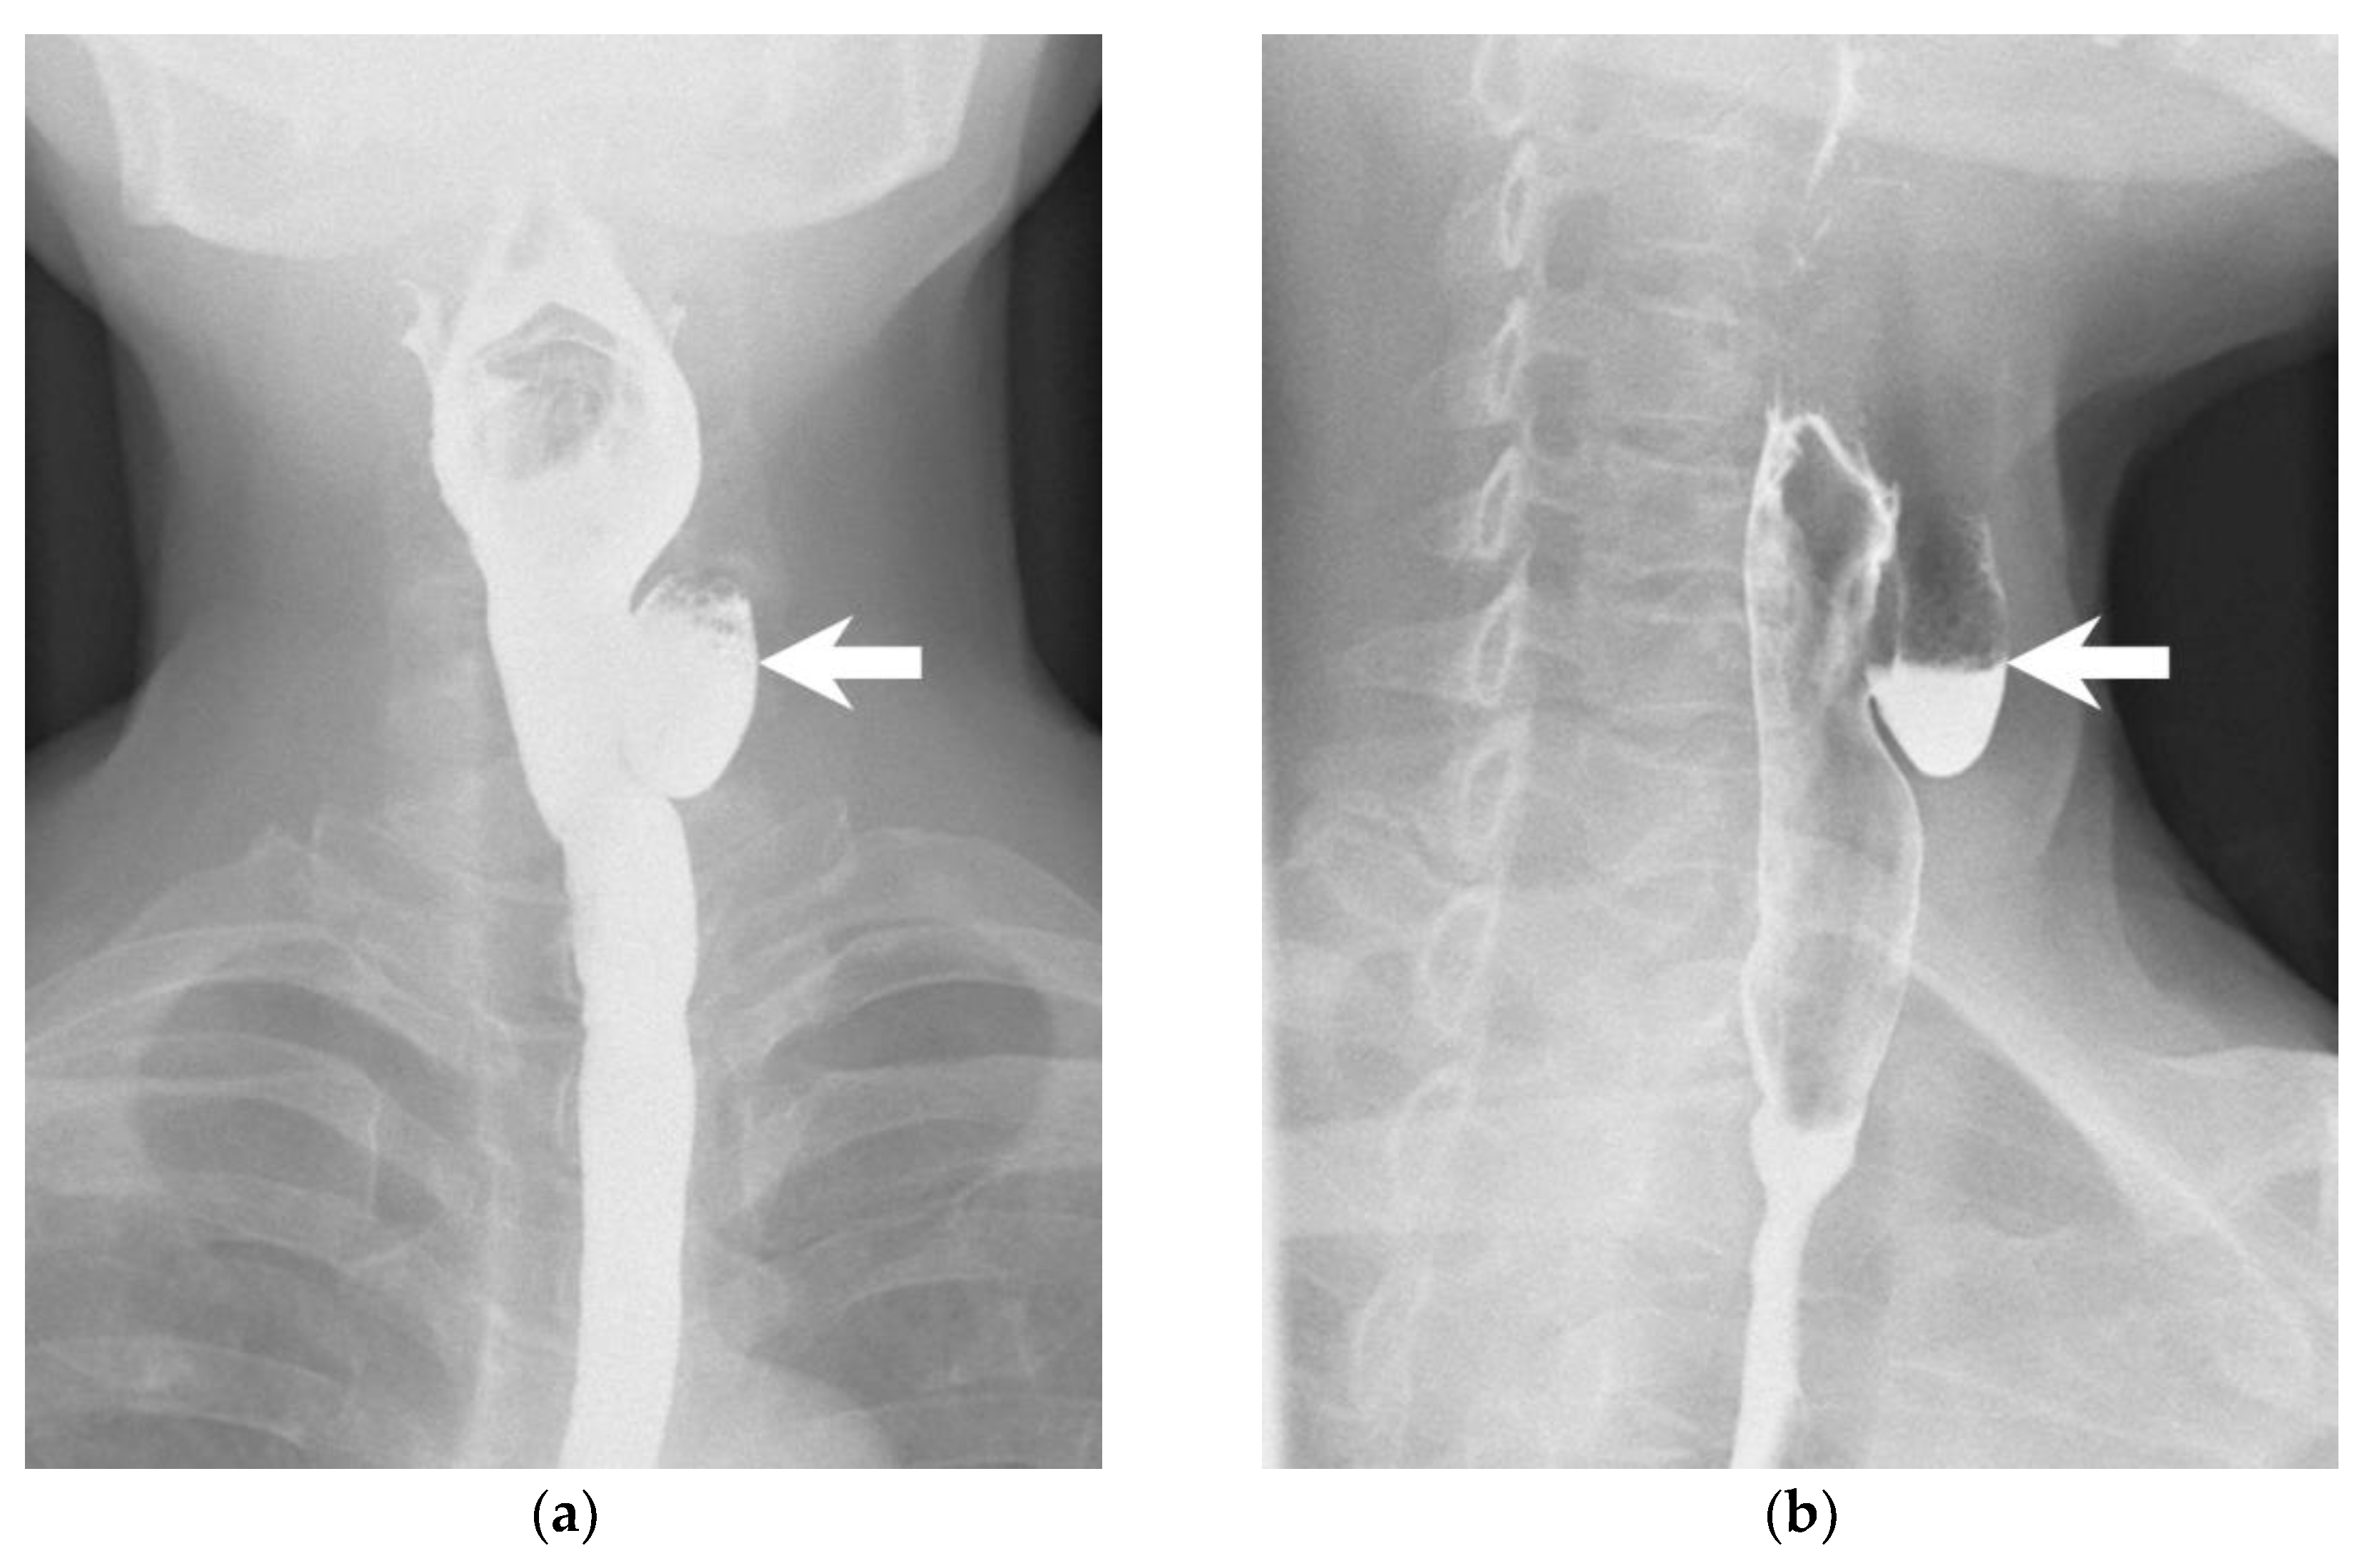

How Soda Ingestion Facilitates the Distinction between a Killian–Jamieson Diverticulum and a Malignant Thyroid Nodule